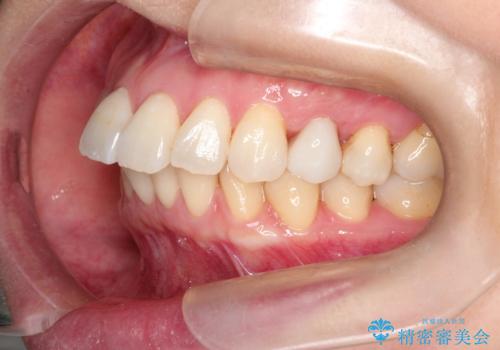

【インビザライン 】前歯を下げたい

- 前歯の凸凹と、前突を主訴に来院されました。

インビザライン にて治療を行なっております。

治療期間中はゴムかけを行なってもらうことで、前歯を下げることができました。